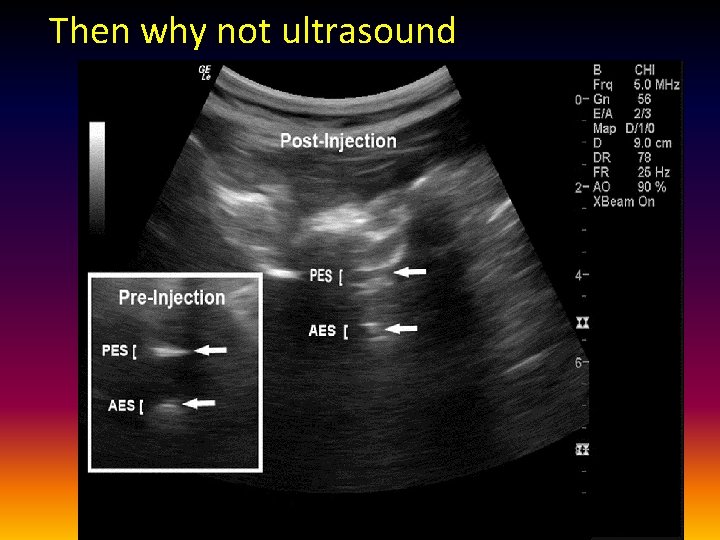

Then why not ultrasound